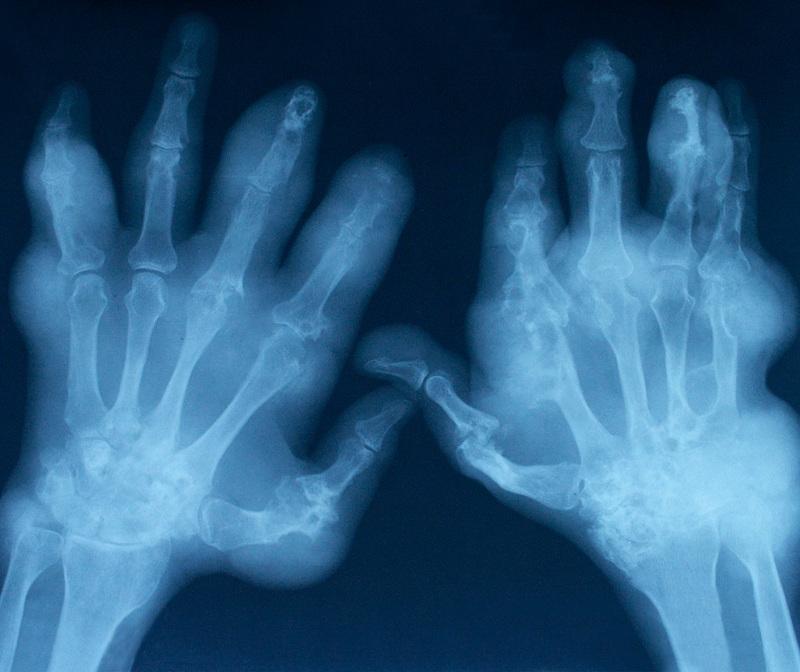

Esta é uma das doenças reumáticas mais frequentes que existem e é produzida pelo desgaste da cartilagem, que provoca diversos problemas no movimento das articulações. É bem mais comum nas mulheres do que nos homens, e pessoas cada vez mais jovens padecem desta doença, por isso é importante saber como prevenir a artrose e cuidar da nossa saúde. Em umComo.com.br damos algumas dicas a respeito deste assunto.